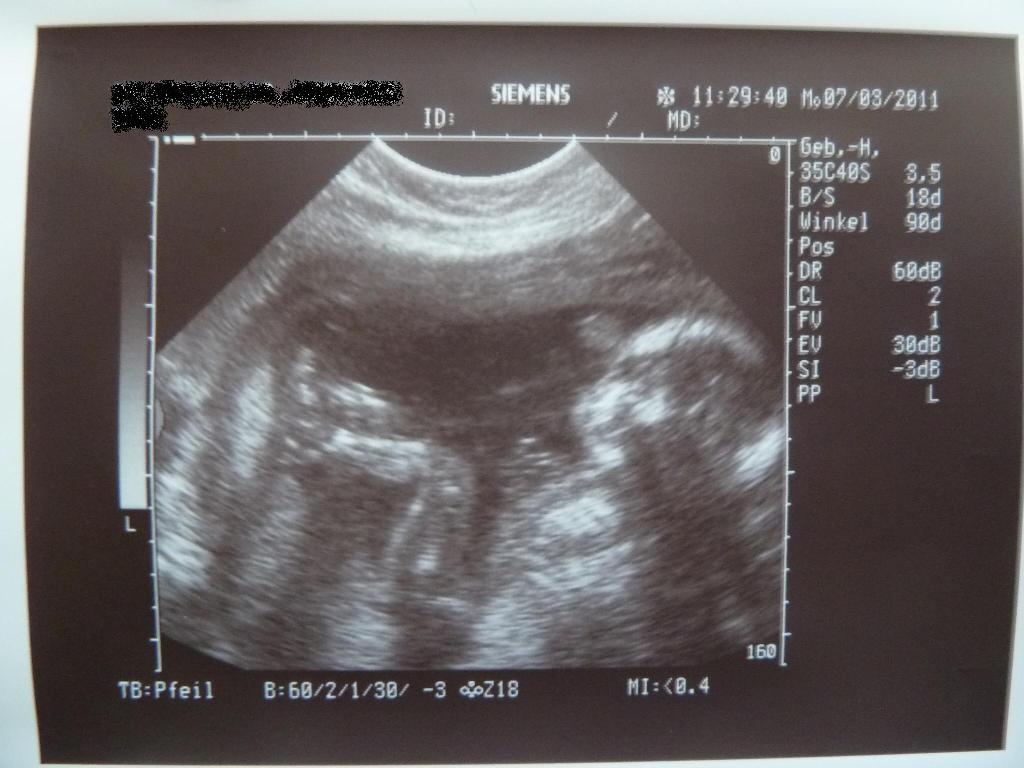

@all: war heute in der Kiwu zum Ultraschall. Ursprünglich wollte ich den Termin absagen, aber nach dem Gruseltermin letzten Montag habe ich mir das ganz schnell anders überlegt…So konnte ich heute endlich mal wieder ausführlich mein Babylein ansehen und danach ging es mir auch gleich vieeeeel besser. Habe heute auch endlich mal wieder ein paar Bildchen bekommen. Die stelle ich euch gleich mit ein. Der Kinderwagen wurde heute geliefert und so habe ich gleich mal fleissig alles geknipst. Bilder folgen. Seid alle lieb gegrüßt!!!